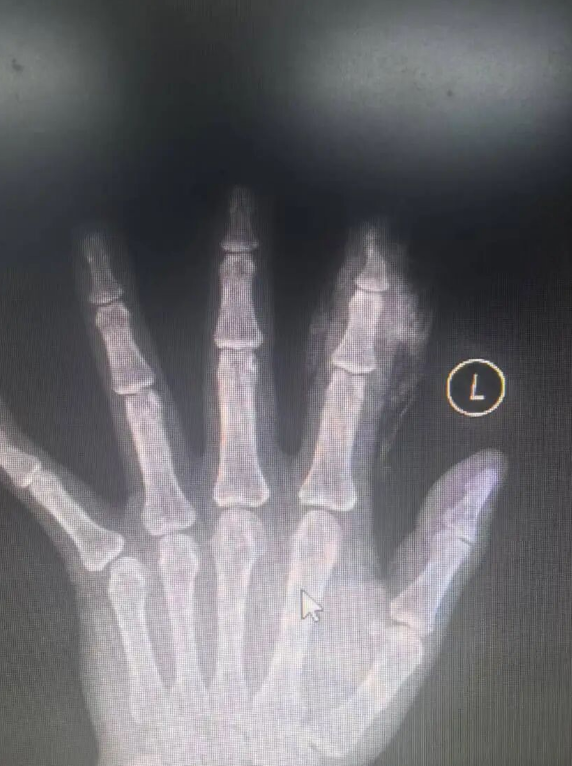

患者王先生,在工作期间不慎被角磨机割伤左手食指,瞬时出现剧烈疼痛,随即由同事陪同前往平度市人民医院急诊科就诊。接诊后手足外科医生对其进行了详细检查,结合查体X线发现患者远节指骨及软组织部分缺损,体格检查见示指末节指腹桡侧缺损,深达骨质,甲床只有少部分残留。如果为患者行传统的手术方案,虽然可以促进伤口愈合,但造成手指短缩,对以后生活质量及工作都会带来影响。

平度市人民医院手足外科团队在经过细致缜密的术前讨论后与患者家属交代病情及治疗方案,在手足外科主任张春龙带领下为王先生实施“手指指动脉逆行皮瓣修复+自体取皮植皮术”,不仅保留了患指指体长度,还可以保留指甲,术后手指皮瓣血运良好,手指长度基本保留。术后2周回院复诊拆线,对王先生的生活、工作基本无明显影响。